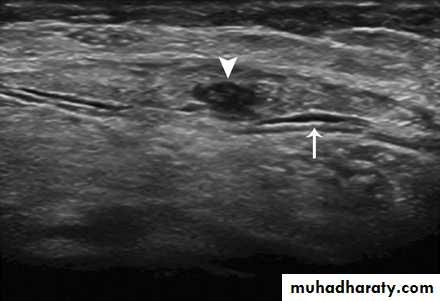

The use of ultrasonography to diagnose acute and chronic gout is increasing . The characteristic findings are a superficial, hyperechoic, irregular band on the surface of articular cartilage, the so-called 'double contour sign' or 'urate icing', and nonhomogeneous tophaceous material surrounded by an anechoic rim. MRI and CT are even more sensitive than ultrasound at detecting gout [Thiele and Schlesinger, 2007; Wright et al. 2007; Dalbeth and McQueen, 2009].

54-year-old woman with gout, palpable mass, and painful dorsiflexion of foot. Sagittal ultrasound shows partial rupture of Achilles tendon (arrowhead), thickening, and surrounding fluid (arrow).